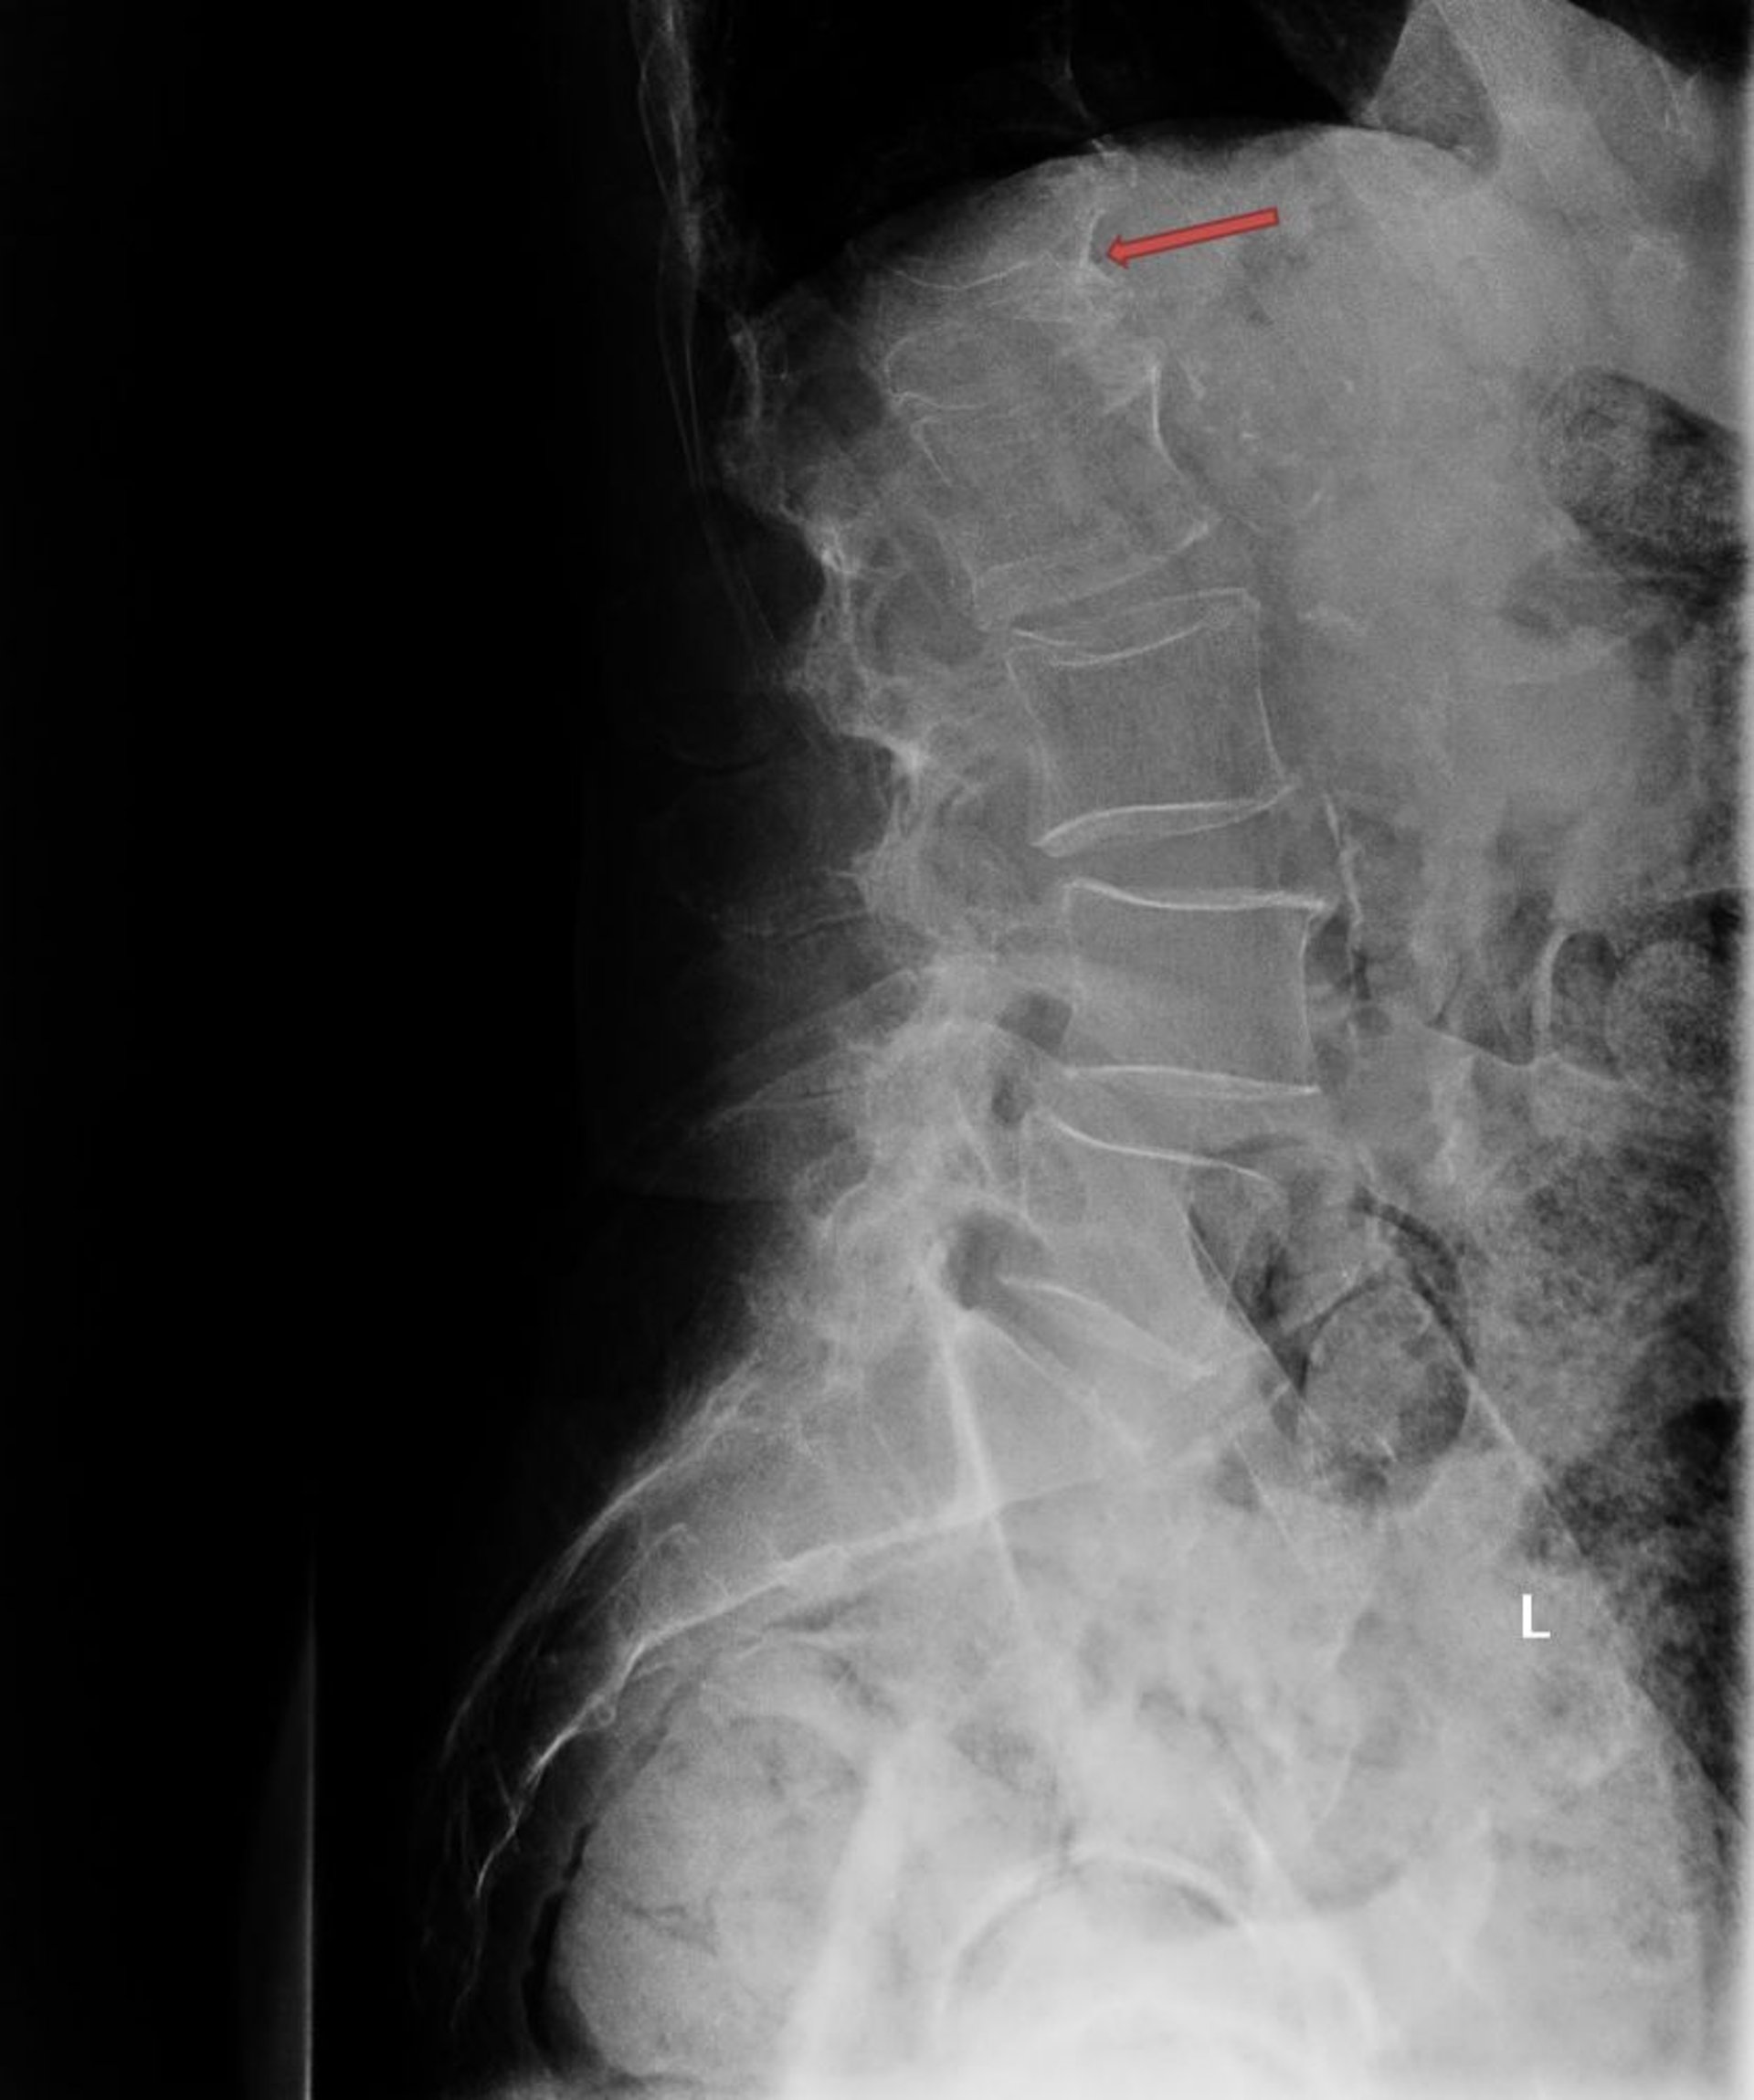

This radiograph shows a severe osteoporotic compression fracture of the first lumbar vertebra (L1; arrow).

Photo courtesy of Marcy B. Bolster, MD.